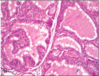

graves disease

obviously hyperfunctioning gland, hyperplasia, and hypertrophy of follicular cells.ar cells